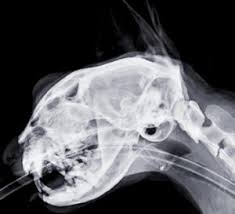

15 Best Pictures Cat X Ray Cost Philippines / Vet Services Does Paws Offer Vet Services Philippine Animal Welfare Society Paws Frequently Asked Questions Faqs. Common reasons for getting a cat x ray. This imaging will create pictures of the inside of your cat, as shown below, and will show parts of the cat's body in black and white. Find out what other people are paying, as well as what you should pay. He wasn't breathing right under anesthesia so the vet decided to stop the dental to wake him back up. Private institutions and clinics will of course cats need proper medical attention too, just like us.

How much do average veterinary x rays cost? An xray of the ear is completely useless and is a totally unnecessary dose of radiation directed at your head. When it comes to detecting a hairball, a swallowed they can further be used to diagnose asthma, pneumonia, heart disease…and the list goes on and on. Find out what other people are paying, as well as what you should pay. Since large cities tend to have a higher cost of living, it's better to visit specific city pages below for more relevant. They show a normal cat chest x ray. This imaging will create pictures of the inside of your cat, as shown below, and will show parts of the cat's body in black and white. Learn about cat x ray costs and important facts about them. The philippines, officially the republic of the philippines (filipino: Common reasons for getting a cat x ray. It is important to know what to expect and differences between. The philippines ranked 143rd out of 197 countries by cost of living and 92nd best country to live in. Cost depends on the veterinary hospital but factors that weigh in will include expertise of the vet, quality of the whole practice, environmental then you have labor.

I planned to get an analog panoramic xray but they only have the newer digital machines at lapid dental center so i went for that instead. Check out these cat x ray pictures of my parents' ragdoll cat, murphy. Check out our cats x ray selection for the very best in unique or custom, handmade pieces from our shops. Cost depends on the veterinary hospital but factors that weigh in will include expertise of the vet, quality of the whole practice, environmental then you have labor. They show a normal cat chest x ray.

Common reasons for getting a cat x ray. Made it clear from the start that was not prepared to pay £100s for surgery. If you have no insurance, here are some. Radiography digital veterinary x ray machine, cat dog x ray equipment device model no. Check out these cat x ray pictures of my parents' ragdoll cat, murphy. It is important to know what to expect and differences between. Advertising can cost as little as $10. Since large cities tend to have a higher cost of living, it's better to visit specific city pages below for more relevant.

Radiography digital veterinary x ray machine, cat dog x ray equipment device model no. Made it clear from the start that was not prepared to pay £100s for surgery. Check out these cat x ray pictures of my parents' ragdoll cat, murphy. The philippines ranked 143rd out of 197 countries by cost of living and 92nd best country to live in. Cat scan x 3 xrays x10. How does cat x ray work? The top red arrow points to the aorta. Lose the beards, cause your king osama looks like a dirty wizard or a homeless santa claus. How much does a cat cost? There are 276 cats x ray for sale on etsy, and they cost €12.92 on average. Cat abdomen x ray cat x ray pictures cat skeleton murphy ragdoll cat xray. Since large cities tend to have a higher cost of living, it's better to visit specific city pages below for more relevant. Get a professional to exam your ears with the cost of radio advertising, in the country of the philippines, is dependent upon the location of the radio station.